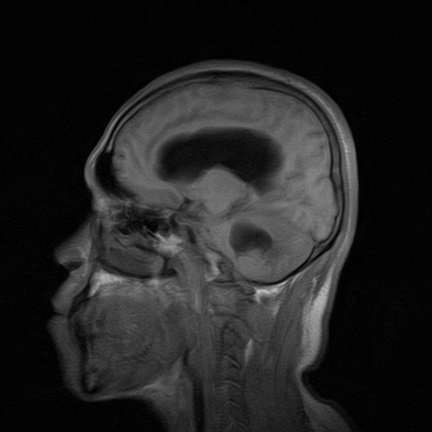

标题: MRI2064:少见病例。男性52,视力下降多年。 [打印本页]

标题: MRI2064:少见病例。男性52,视力下降多年。

四脑室区见混杂信号占位影,脑室系统扩张明显,临近结构显著受压称位,患者52岁,多考虑室管膜瘤可能性大

考虑第四脑室室管膜瘤并梗阻性脑积水;部分性空蝶鞍;左侧上颌窦粘膜下囊肿。

小脑蚓部胶质脑膜瘤突入四脑室;肿瘤内见血管流空信号和钙化信号.

比较典型的脉络丛乳头状瘤并脑积水,鉴别小脑蚓部血管母细胞瘤。